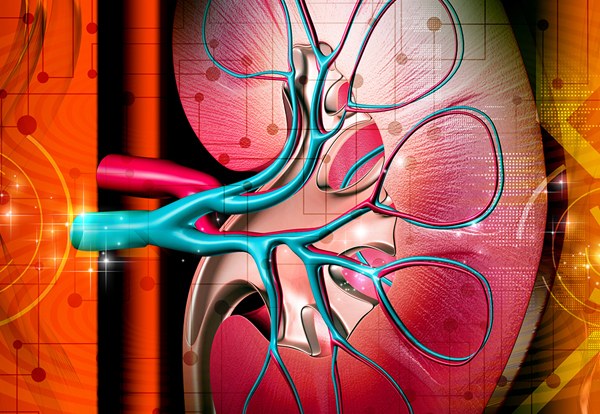

Нефроптоз почки

Нефроптоз правой почки – это патологическая подвижность органа. Особенность этого органа в том, что он не имеет фиксирующих связок. Следовательно, он более подвержен смещению.

Нормальная анатомическая подвижность почек оберегает их от травмирования во время резких движений телом. Максимально они перемещаются примерно на 2 см. А вот при патологической подвижности они опускаются в брюшную полость вниз. В тяжелых случаях почка может быть даже в полости малого таза.

По мере того, как развивается болезнь, почечные магистральные сосуды вытягиваются и перекручиваются. Диаметр артерии может уменьшиться в 2 раза, настолько же вырасти ее длина. То же происходит и с почечной веной.

Изменение диаметра и длины почки приводит к кислородному голоданию органа и повышению давления в вене.